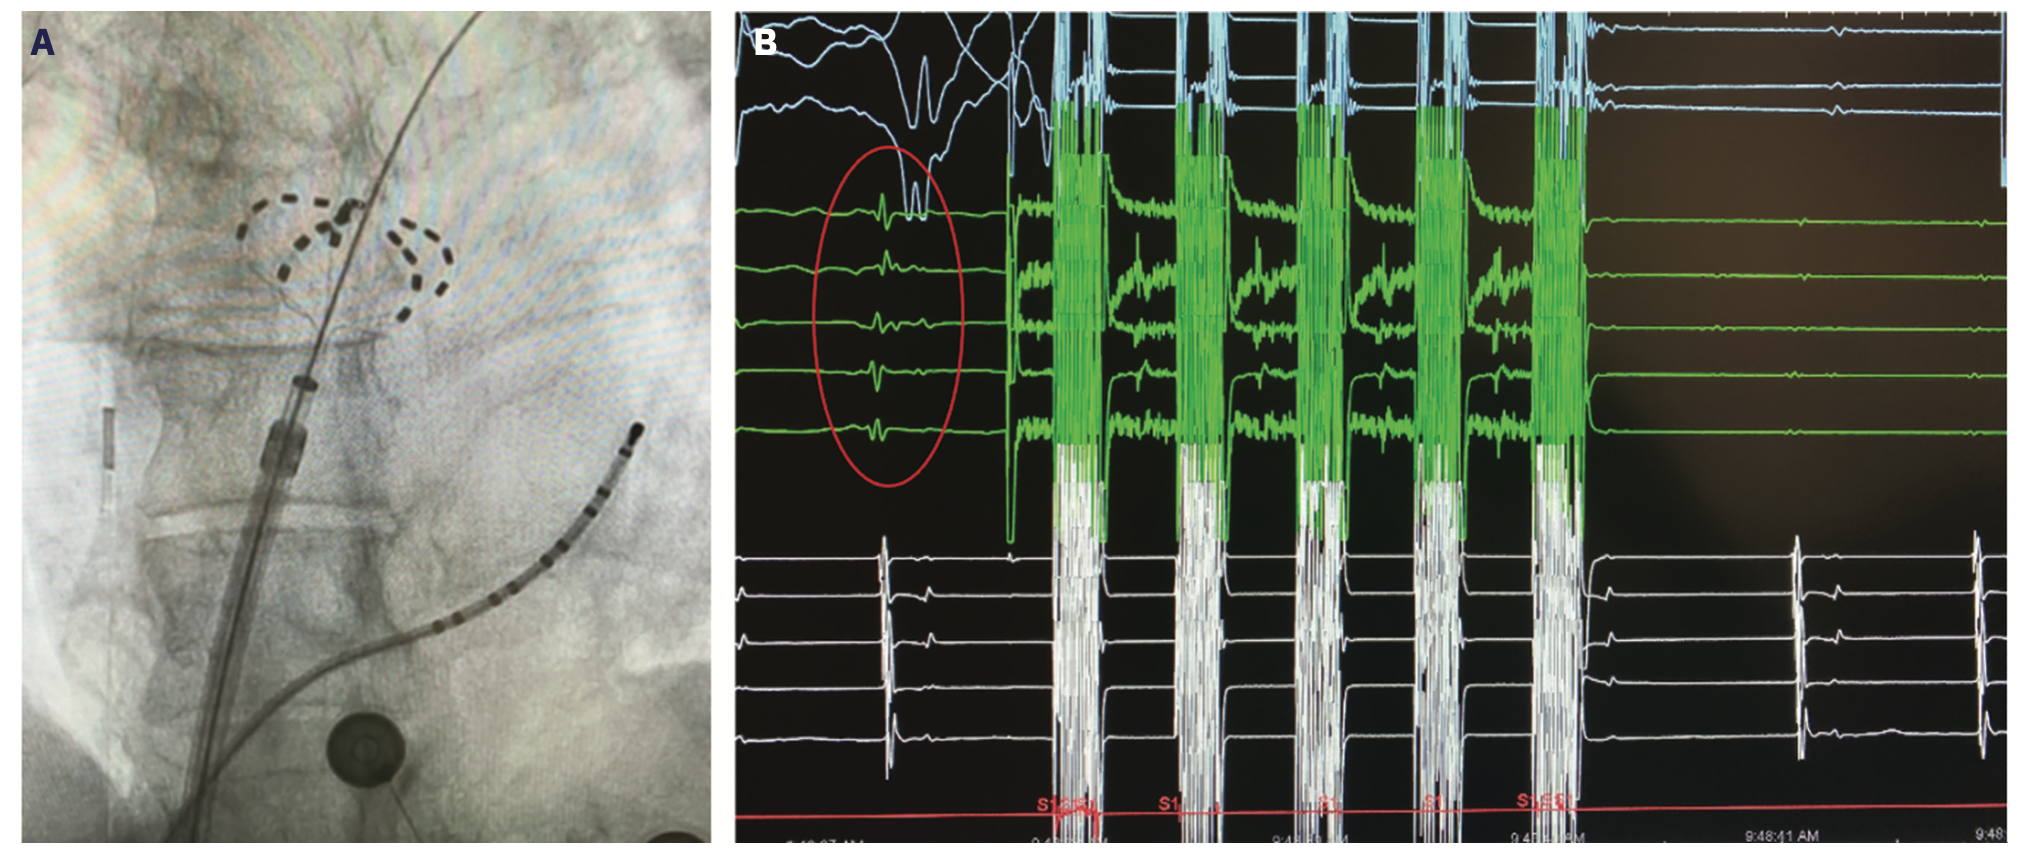

Reddy et al reported the first clinical experience in 22 patients with paroxysmal AF using pulsed electric field ablation for PVI (15 endocardial and 7 epicardial).25 Catheter-based PV isolation using the Farawave catheter was 100% successful using a total electroporation delivery time of less than 60 seconds per patient (Figure 1). The epicardial box lesion was done using a linear catheter around the PVs and successful in 86% of patients using 2 lesions per patient. The IMPULSE (n = 40) and PEFCAT (n = 41) trials also examined patients with paroxysmal AF using both monophasic (IMPULSE) and biphasic (PEFCAT) waveforms with the Farawave catheter.26 PVI was achieved in 100% of patients, with no reconnections noted during the 20-minute waiting period or with provocative adenosine testing. Monophasic waveforms required general anesthesia and paralytic agents because of profound skeletal muscle contraction. The biphasic waveform cases were better tolerated due to less contraction and performed under conscious sedation. In follow-up, no patients had phrenic nerve palsy, esophageal injury, or PV stenosis.27 A 1-year follow-up study showed durable PVI in 84.8% of PVs remapped at 90 days in 110/121 patients in the IMPUSE, PEFCAT, and PEFCAT II studies.28 Freedom from atrial arrhythmias at 1 year in the entire cohort was 78.5 ± 3.8%. The PULSED AF Pilot Trial (n = 38) for paroxysmal AF using the PulseSelect PFA System (Medtronic) also showed 100% acute PV isolation with no adverse events such as phrenic nerve injury, esophageal injury, or stroke.29 The single-arm, multicenter PersAFOne study in persistent AF patients from Homolka Hospital in Prague, Czech Republic, and Clinical Hospital Center Split in Split, Croatia, used the pentaspline Farawave catheter for PVI and posterior wall isolation (PWI) and a focal PFA catheter (Faraflex, Boston Scientific) for cavotricuspid isthmus (CTI) ablation.30 Acute isolation of the PVs and PW was achieved in all 25 patients and CTI block was achieved in 13/13 patients. Postprocedural esophagogastroduodenoscopy and computed tomography scans showed no evidence of esophageal injury or PV stenosis. Invasive remapping in 22/25 patients showed 96% of PVs isolated at 3 months and 21/21 PWs were isolated. Another trial that used the lattice tip catheter in a first-in-human experience showed that the Sphere-9 catheter could be used to toggle between RF and PFA or use PFA alone in both paroxysmal and persistent AF patients with good efficacy and safety.31 Loh et al similarly showed that PFA using a proprietary 14-polar single-shot circular catheter could achieve acute bidirectional isolation in 10 patients in another first-in-man study.32

In the United States and internationally, there are over 20 trials listed as active on www.clinicaltrials.gov for PFA in patients with AF. Many of the trials are exclusive to international sites in Europe or Asia. Three clinical trials with sites in the United States are active and recently finished recruiting. The ADVENT trial compared the Farapulse PFA System to current standard of care ablation systems (RF or cryoablation) in paroxysmal AF. The PULSED AF study was a single-arm study using the PulseSelect PFA System in either paroxysmal or persistent AF patients (Figure 2). The admIRE study evaluated a circular multielectrode PFA catheter (VariPulse, Biosense Webster, Inc, a Johnson & Johnson company) in a single-arm study of paroxysmal AF patients (Figure 3). Ongoing and actively recruiting studies include the Sphere-9 lattice PF/RF system compared to RF ablation in a 1:1 randomization in persistent AF patients in the SPHERE Per-AF trial.